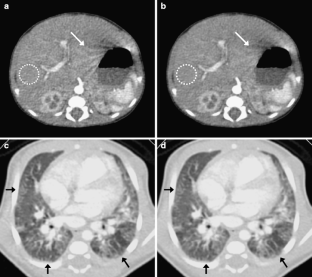

Fig 5.